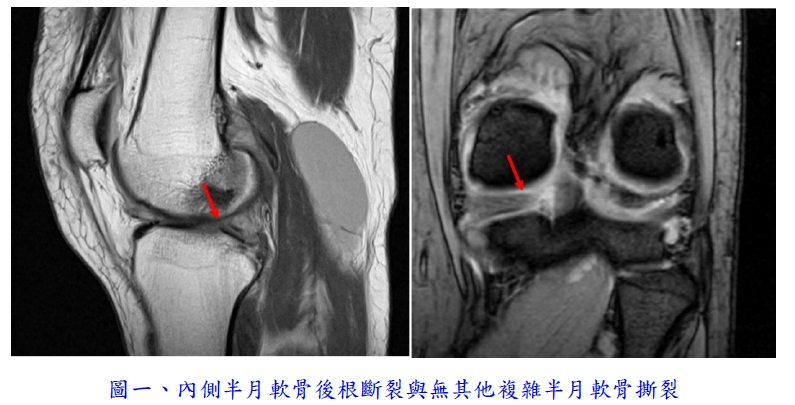

如年輕或運動需求大的病患,常見十字韌帶斷裂或半月軟骨撕裂,通常即便經過保守治療,仍容易出現後續症狀甚至二次傷害,建議及早轉介處理。前十字韌帶斷裂通常需重建新的韌帶,半月軟骨撕裂則需要進行關節鏡手術縫合。中年病患方面,若無明顯受傷史,但在日常生活中突發嚴重膝蓋疼痛,且X光結果未有嚴重退化、經過保守治療仍未改善者,通常可能是半月軟骨後根撕裂,也建議盡早轉介至醫院,及早接受關節鏡修補手術,可延緩膝關節退化、降低未來人工關節置換和骨壞死的機率,並改善生活功能(圖一)。